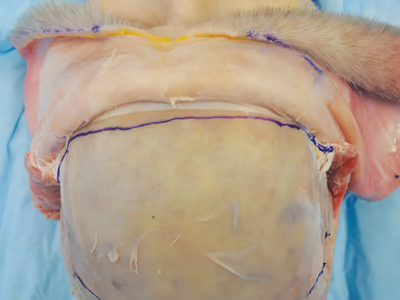

Composite facial allografts have become increasingly popular in the reconstruction of complex facial defects. Good to excellent aesthetic results can be achieved, particularly when a foundation of donor skeleton has been transferred...